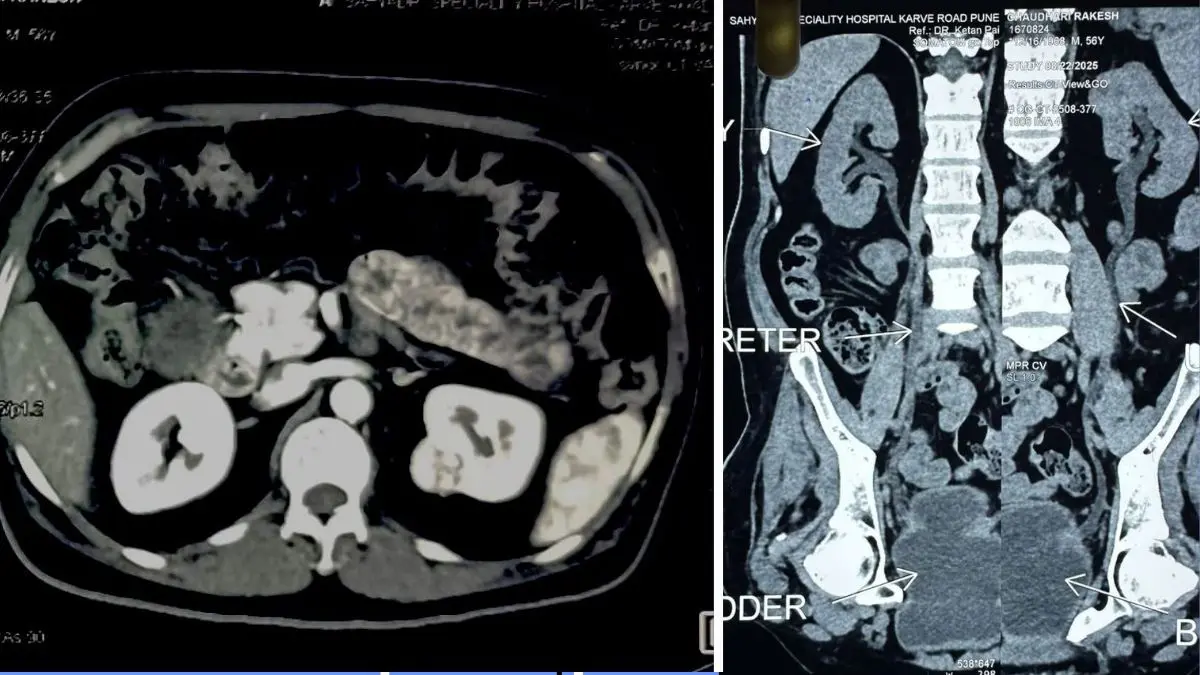

દર્દીને CECT (એબડોમન + પેલ્વિસ) એટલે કે પેટના ભાગનો સિટી સ્કેન કરાવતા આ વખતે ડાબી કિડનીના ઉપરના પોલના મધ્ય ભાગમાં 34 × 28 સાઇઝ નો કેન્સર વાળો ભાગ જોવા મળેલ. દર્દીના શરીરના અન્ય ભાગમાં કેન્સરની અસર છે કે નહીં તે જાણવા માટે ડોક્ટરો દ્વારા દર્દીનો PET- સ્કેન પણ કરાવવામાં આવ્યો હતો જેમાં સદનસીબે બીજી કોઈ જગ્યાએ કેન્સર ફેલાયું હોય કે કેન્સરની અસર હોય તેવું જણાયું ન હતું.

દર્દીના સીટી સ્કેન તેમજ પેટ સ્કેન ના રિપોર્ટો તથા દર્દીને ભૂતકાળમાં થયેલા કિડનીના કેન્સર ને ધ્યાનમાં રાખીને સિવિલ હોસ્પિટલના યુરોલોજી વિભાગના વડા ડોક્ટર શ્રેણિક શાહ અને તેમની ટીમના નિષ્ણાત ડોક્ટરો દ્વારા ખૂબ જ જટિલ એવી લૅપેરોસ્કોપિક લેફ્ટ પાર્ટિયલ નેફ્રેક્ટોમિ એટલે કે દૂરબીન થી દર્દીની કિડનીના કેન્સરની અસરવાળા ભાગ માત્રને દૂર કરવા નું સફળતાપૂર્વક ઓપરેશન કરવામા આવ્યું. એનેસ્થેસિયા ડો. નિલેશ સોલંકી એન્ડ ટીમ દ્વારા આપવામાં આવ્યો.. સર્જરી દરમિયાન અને સર્જરી બાદ પોસ્ટઓપરેટિવ સમય પણ કોઈપણ તકલીફ વગરનો રહેતા દર્દી ની સ્થિતિ સ્થિર જણાતા ડિસ્ચાર્જ આપી ઘરે જવા રજા આપવામાં આવી હતી.